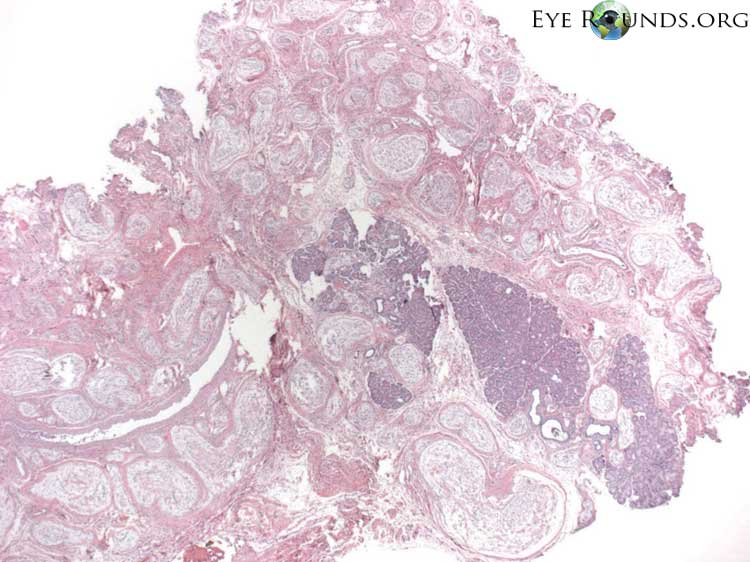

Clinical Images

High-resolution clinical photographs showing various presentations of malignant melanoma of the choroid.